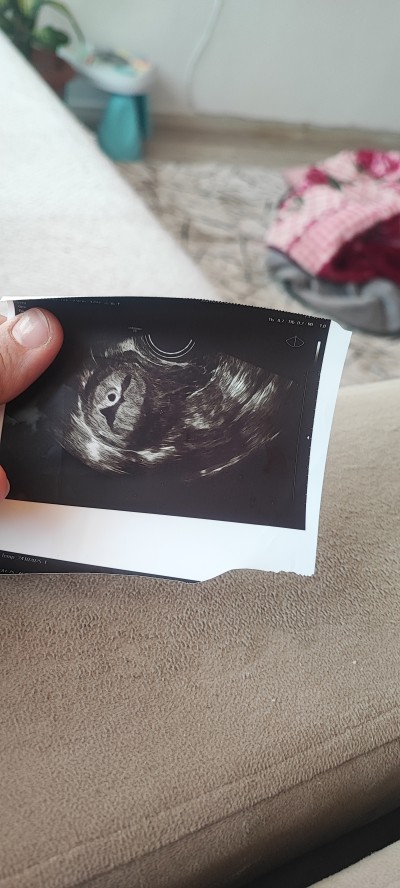

Kızlar merhaba 5+ 3 günlük gebeyim bu gün doktora gittim doktor kücük bir kese var dedi mol gebelik olabilir dedi basına böyle bişey gelen varmı yardımcı olun lütfen Upload failed: [object Object]

Mol gebelik olabilir mi

image

Banada aynısını dediler perinatoloji ye yönlendirdi gitmedim beta degerlerimde aşırı bı yükselme vardı normalde olması gerekenin bi kaç kat ustundeymis falan ya mol gebelik dedi yada çoğul gebeliktir demişti çoğul değildi tek çocuk ama mol gebelikte değil mol gebelik olunca sonlandırmak istiyolar sakın tek doktora görünüp hamileliğini sonlandirma başka birine daha görün en kötü bekle bı kaç hafta daha attığın resimde de mol gebelik gibi durmuyo  normalde mol gebelikler de kere üzüm gibi olurmuş bı kaç tane kese olurmuş vs sendeki öyle bıseyde değil benmki gbi drek beta değerine göre yorum yapmış bence ben senin yerinde olsam bı kaç hafta daha beklerim sonra başka doktora daha görünür öyle hareket ederim ki bende öyle yaptim

Anladım canım ben foto eklicem bak üzüm salkımı gibi durmuyormu

Ya hafif bı benzerlik var ama emin ol belki beta degerin yüksek olmasa onu bile anlamicaklardi yine de emin olmadan işlem yaptırma hayırlısı neyse o olsun

Bu resim sağda üzüm salkımı gi o duruyor